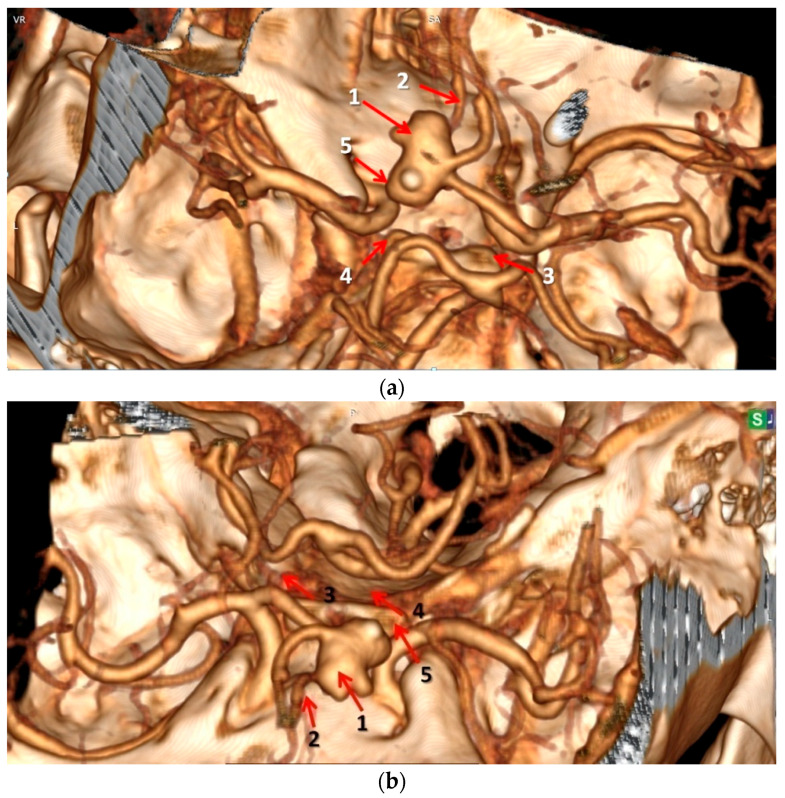

Methods: We investigated the anatomical variants of the CW associated with the occurrence and rupture of AcoA aneurysms by performing comparative analyses, in the same patients, of postmortem autopsy data with antemortem computed tomography-angiography (CTA) results obtained in the first 48 h after the onset of subarachnoid hemorrhage. Our retrospective observational study identified the anatomical variants of the CW at autopsy in 16 deceased adult Romanian patients with AcoA aneurysms over a 12-year period (2010-2022).

Results: The autopsy findings revealed that the AcoA ruptured aneurysms had a mean external diameter of 9.50 mm, and 71.4% of them presented three or four anatomical variants inside the same CW. The initial antemortem CTA examination correctly located the AcoA aneurysms in all cases (100%), and an anatomical variant of the CW was only noted in 18.75% of patients. The final postmortem re-analyzed the same CTA images identified in all cases (100%), focusing on both the AcoA aneurysm and all anatomical variants of the CW found during the autopsies.

Conclusions: Although it was previously thought that the occurrence of AcoA aneurysms is related only to the hemodynamic changes induced by the nearby arterial anatomical variants, we identified the simultaneous involvement of at least one hypoplastic artery and one or two PCA fetal-type anatomical variants that were located in both the anterior and posterior parts of the CW. Furthermore, if sufficient time is devoted to the CT-angiography analysis and interpretation of the images, anatomical variants of the circle of Willis associated with AcoA aneurysms can be identified as accurately as they are in invasive postmortem autopsy examinations.